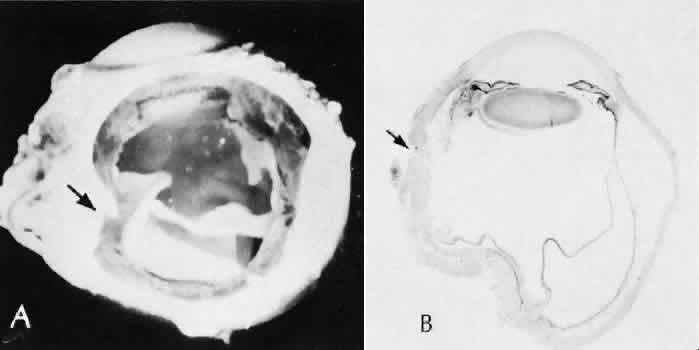

Cyclocryotherapy, cyclodiathermy (Fig. 20), and therapeutic ultrasonography apply energy directly to the pars plicata and cause lysis of the ciliary muscle and occlusion of the vascular supply, leading to extensive necrosis and scarring. Pressure lowering is accomplished by a reduction of aqueous production. Heat applied to the sclera may cause necrosis and localized scleral thinning. Cold applied to the sclera, unless extreme, does not cause any clinical or histologic changes.

Fig. 20. Cyclodiathermy treatment of the ciliary body to control glaucoma. A. Gross photograph illustrates extensive areas of depigmentation mainly in the region of the pars plana (arrows) rather than the pars plicata. B. Light micrograph of the region of the pars plana illustrates an extensive area of tissue degeneration of the pars plana (between arrows) in the late postoperative course. C. Light micrograph of the destructive effects of cyclocryotherapy also in the region of the pars plana and pars plicata. The ciliary epithelium in the early postoperative period is necrotic and cystic. (Hematoxin-eosin stain; A, × 8; B, × 16.)

Cyclodialysis (Fig. 21) creates a cleft between the sclera and the longitudinal muscle of the ciliary body. Aqueous passes directly from the anterior chamber into the suprachoroidal space. Histologically, the longitudinal muscle of the ciliary body is disinserted from the scleral spur. Diaphanous tissue often is present in the suprachoroidal space along the route of filtration. The presence of this tissue differentiates the surgical site from artifactual disinsertion of the ciliary body, which is a common artifact of ocular tissue preparation.

Fig. 21. Light micrograph of cyclodialysis. The region of the surgical cleft between the longitudinal muscle of the ciliary body and the sclera (arrow) is filled with delicate fibrous tissue. Note the posterior location of the anterior face of the ciliary body and the angle recesses in relationship to the scleral spur (S).